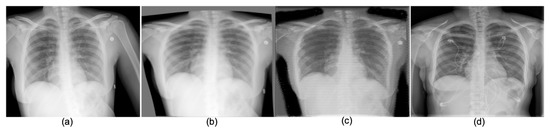

4.3.2. Portable Radiographs Quality Enhancement

| Por.CXR vs. Con.CXR | Enh.CXR vs. Con.CXR | Por.CXR vs. Con.CXR | Enh.CXR vs. Con.CXR | |

| 28.019/0.245 | 30.273/1.798 | 0.936/0.018 | 0.960/0.011 | |

| 28.003/0.236 | 30.437/1.707 | 0.748/0.047 | 0.787/0.045 | |

| 29.009/0.229 | 30.474/1.724 | 0.919/0.021 | 0.955/0.013 | |

| 28.006/0.227 | 30.522/1.662 | 0.729/0.050 | 0.780/0.047 | |

| 28.011/0.205 | 30.407/1.670 | 0.873/0.035 | 0.920/0.021 | |

| 28.009/0.198 | 30.498/1.629 | 0.839/0.044 | 0.910/0.026 | |